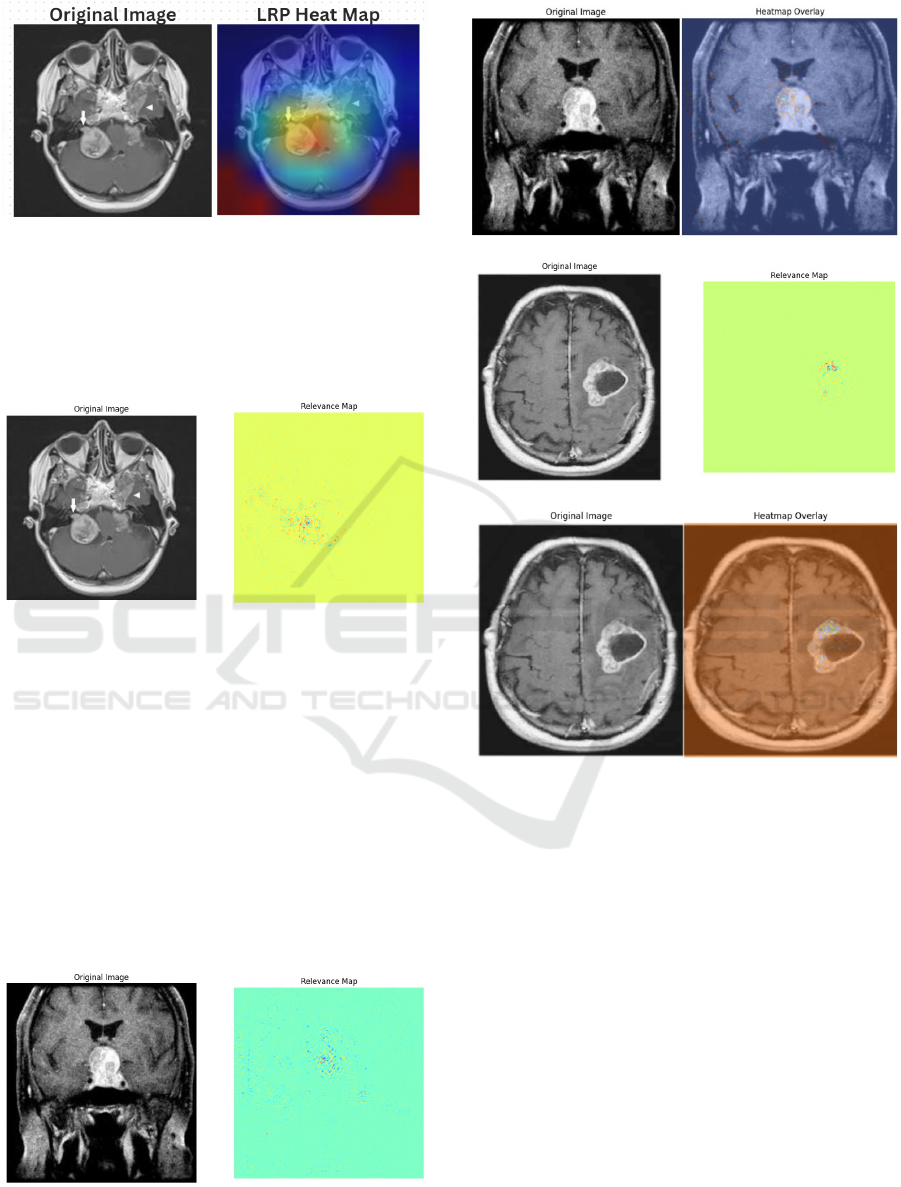

(Pang et al., 2023). Additionally, techniques such

as Layer-wise Relevance Propagation (LRP) have

emerged as powerful tools for explaining classifier

decisions by providing pixel-wise decomposition of

predictions. LRP generates heatmaps that highlight

regions most relevant to a given class prediction, en-

hancing transparency and interpretability (Bach et al.,

2015b). Studies have validated LRP’s utility in multi-

class medical imaging tasks by confirming predic-

tions and identifying biologically meaningful fea-

tures, reinforcing its value in AI-driven diagnostic

systems (Babu Vimala et al., ).